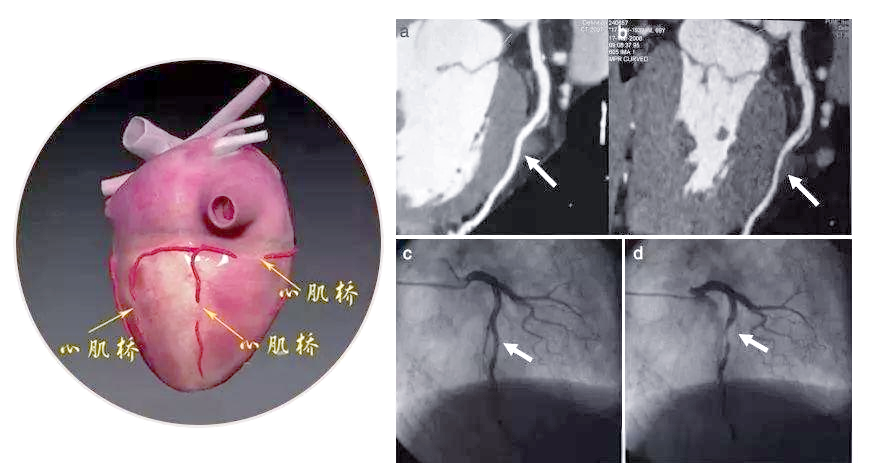

前降支心肌桥疑致急性心肌梗死一例

心肌桥

心肌桥,或称心肌桥冠状动脉,是一种较为常见的先天性冠状动脉畸形

上海中山医院葛均波等提出左前降支心肌桥的葛氏三联征